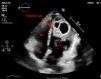

This is the case of a 33-year-old man from Morocco who sought consultation with a 3-month history of dyspnea and chest discomfort. An ultrasound (Fig. 1) identified the presence of a cystic mass in the apex of the left ventricle. Diagnosis was completed with an MRI, which characterized the cyst as hyperintense on T2-weighted images (Fig. 2). Symptoms of cardiac hydatidosis depend on the degree of pericardial and coronary compression, and the mass itself. Transthoracic ultrasound offers good sensitivity and specificity for diagnosis, which was confirmed by pathological anatomy during the intervention, which involved resection of vesicles with protection of the surgical bed using hypertonic scolicidal saline. Upon discharge, the patient remained on albendazole treatment for, at least, 6 months.

Figure 1